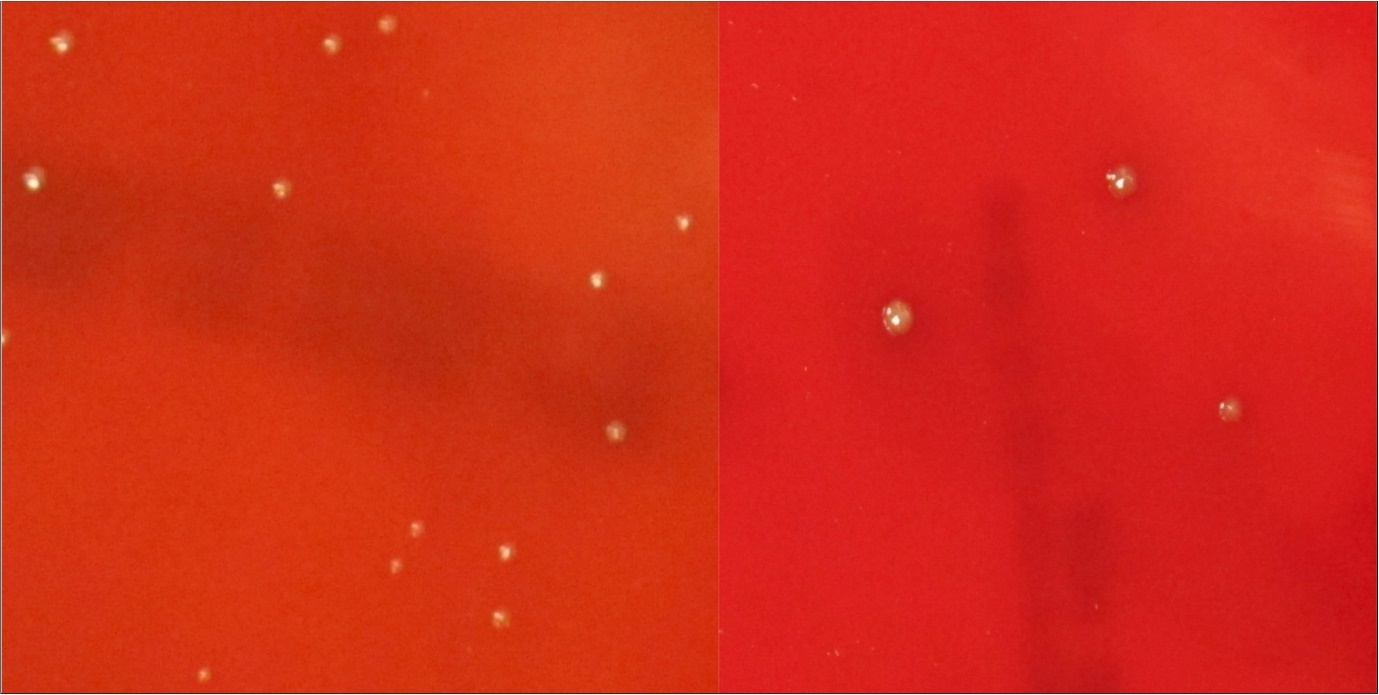

When comparing the kill rate between the control and 120 seconds of sonication, P Gingivalis had a 64% kill rate (Figure 1). When comparing control to all of the time intervals tested, P Gingivalis was only significant at 120 seconds, with nonsignificant results for the lesser time intervals.

Figure 1.Porphyromonas Gingivalis; Culture plates (a) Control, (b) 120 seconds